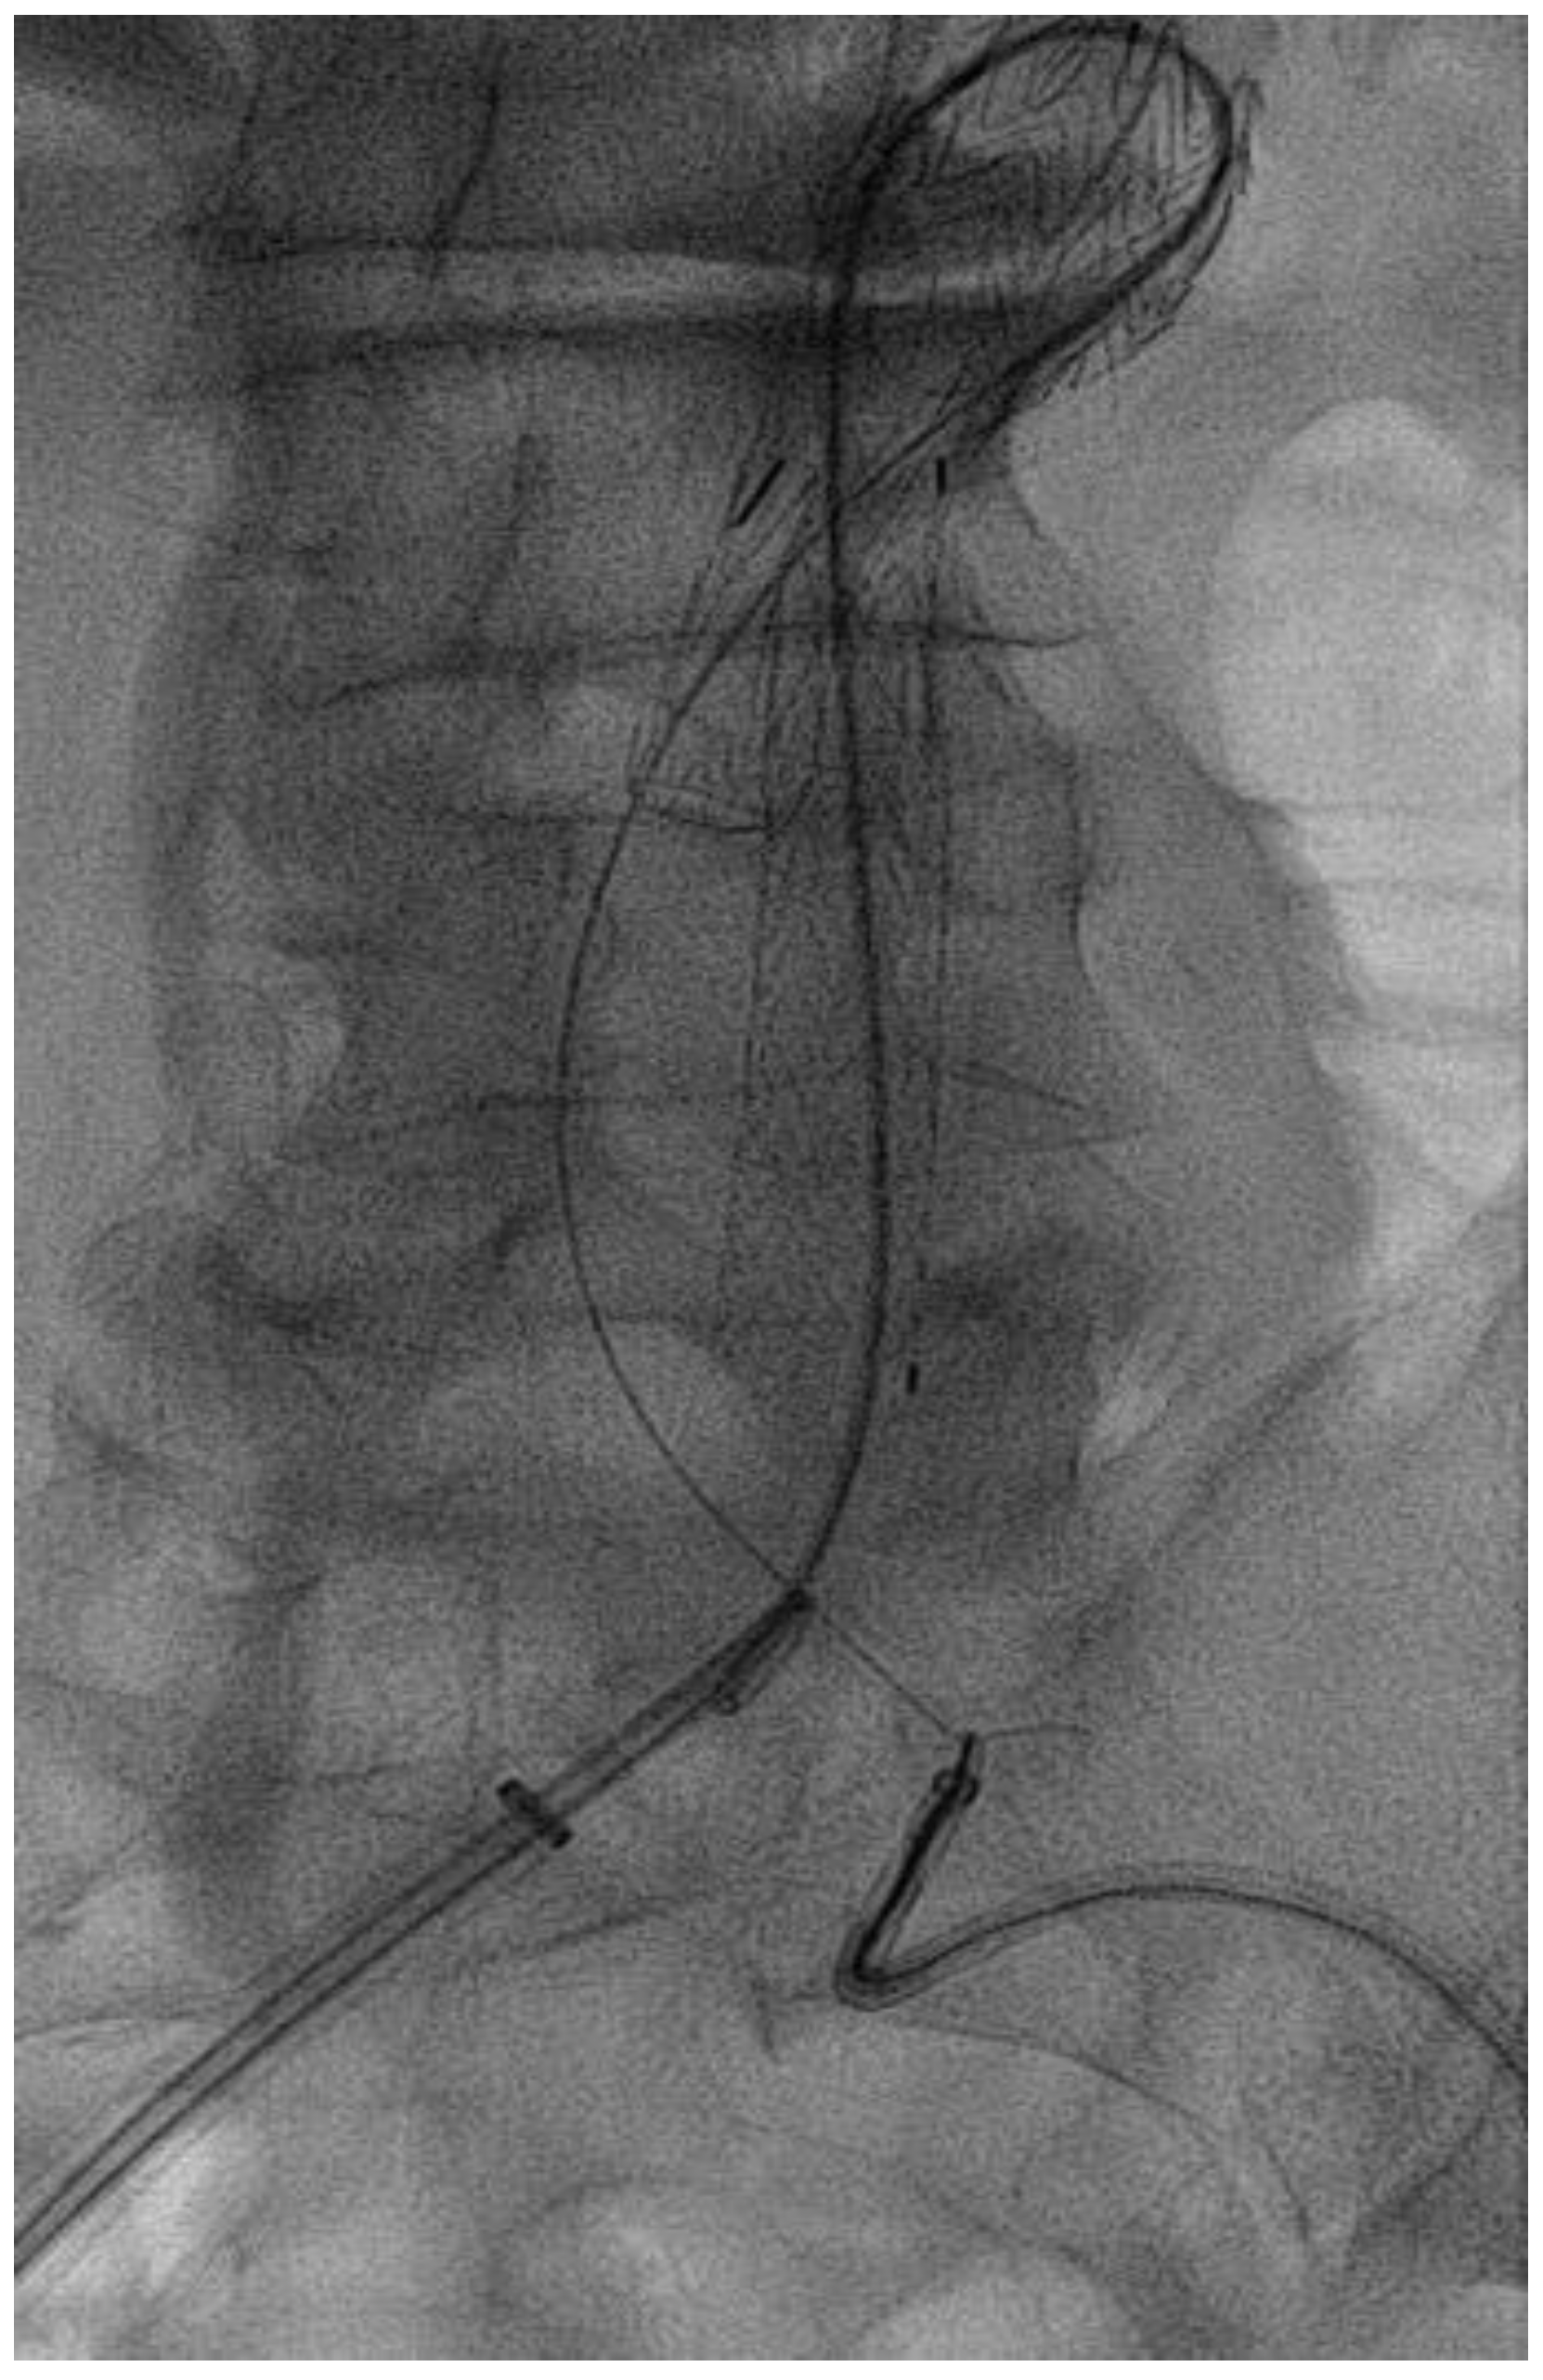

Surgical Technique